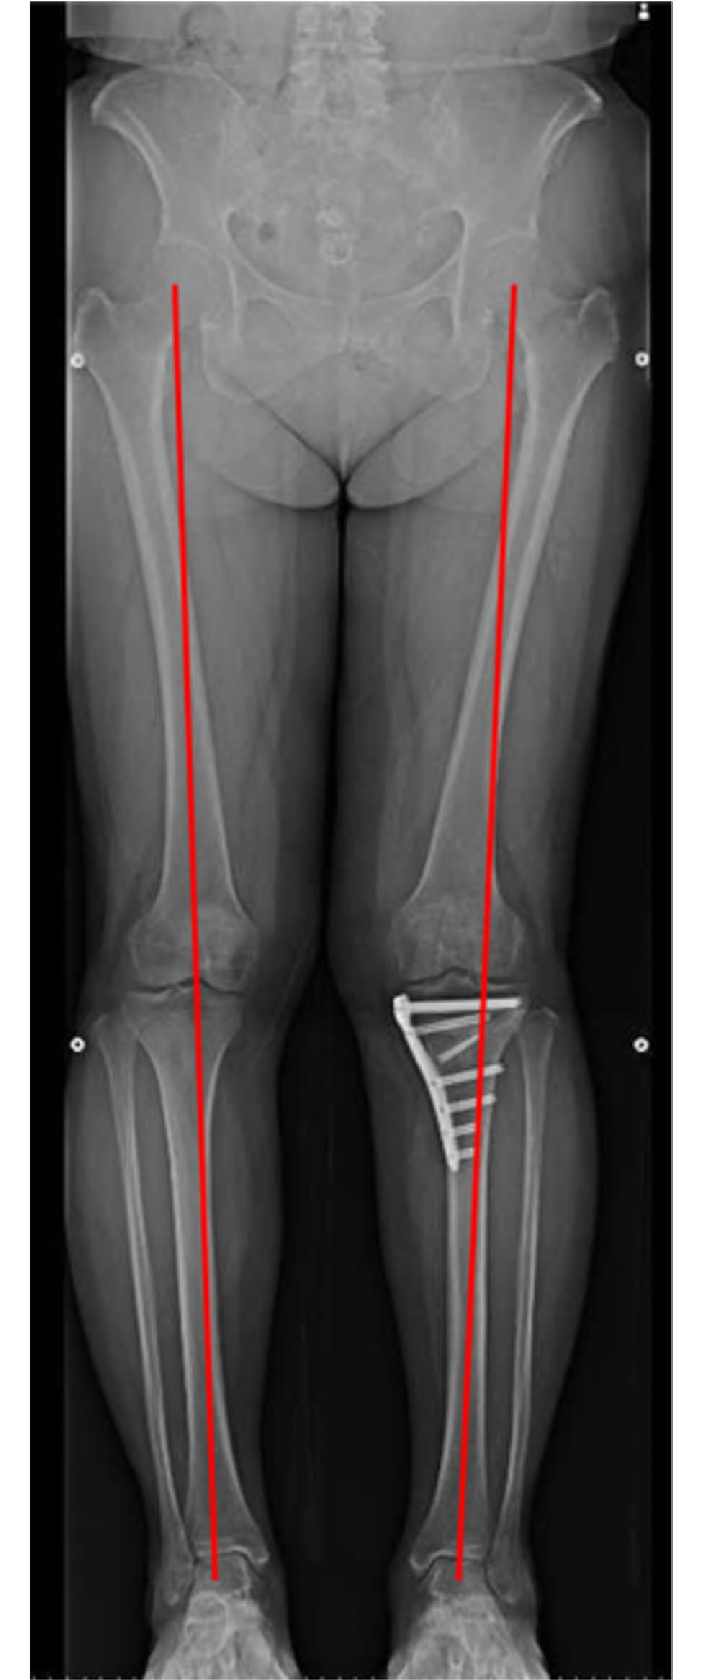

High Tibial Osteotomy (HTO)

HTO is a joint-preserving knee surgery where the leg alignment is corrected to shift weight away from damaged cartilage.